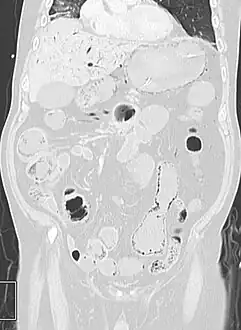

Pneumatosis intestinalis in the coronal computed tomography in lung window. It can be seen next to gas entrapment in the bowel wall and gas in the stomach wall and in numerous vessels, including the portal vein into the liver.

- Coronal reformatted MDCT image showing extensive pneumatosis intestinalis in the left upper quadrant small bowel. The pneumatosis is more cystic and nodular in the small bowel in the midline and the right of midline. This patient had a relatively benign presentation without bowel ischemia and was treated conservatively.